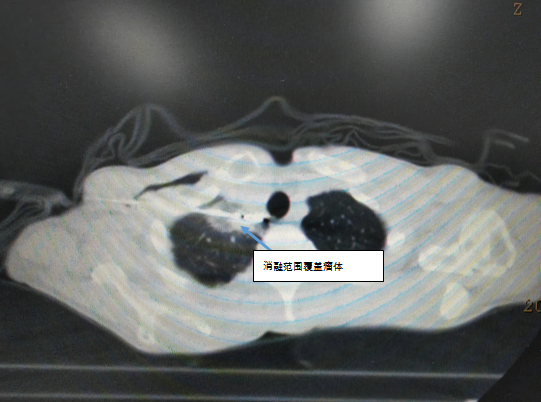

CT引导下肺部肿瘤消融作为新兴的肿瘤微创治疗方法,已广泛运用于原发肺部肿瘤和转移肺部肿瘤的局部治疗,具有创伤小、精准、可重复、安全性高、患者恢复快等特点。对于无法耐受手术切除的早期非小细胞肺癌患者(肿瘤直径2-3cm)进行消融治疗,显示了该项技术在肺部肿瘤治疗中的价值。